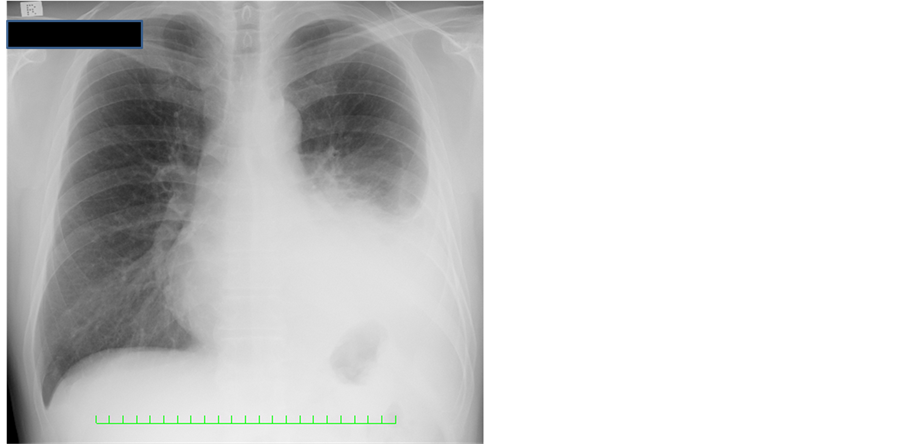

He was admitted to our hospital to receive a detailed examination and appropriate treatment. The results of the peripheral blood cells counts and biochemistry examinations were within normal limits. Tumor markers, in- cluding the carcinoembryonicantigen, cytokeratin 19 fragment and pro-gastrin-releasing peptide, were also within normal limits. Chest computed-tomographic scanning displayed a 5-cm mass in the left inferior lobe (Figure 3(A)), which obstructed the left lower endbronchus, and the lower lobe, except for the S6 segmental le-

Figure 3. Chest computed-tomographic scanning. (A) The arrow shows a 5-cm mass, which obstructed the left lower endbronchus; (B) The arrows show that the tumor invaded the membraneous portion of the left main bronchus and the left upper bronchus with lymph nodal metastsis.

sion, consisted of athelectasis and lymph nodal metastasis (N1+) (Figure 3(B)). The tumor was heterogeneously enhanced by a contrast agent, which continuously invaded the lingular segment of the left upper bronchus and the hilar lymph nodes, and which findings were suspected to invade the left upper lobe. Intrapleural dissemination and malignant pleural effusion were also suspected (cT3N1M1a, c-stage IV). Position emission topography displayed abnormal accumulations of the left hilar lymph nodes and the tumor in the basal part of the left inferior lobe (maximal standardized uptake valuemax, early: 7.0, delay: 9.1). There was no systemic distant metastasis.